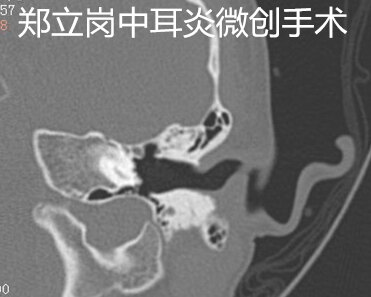

患者黎,男,5岁,广东佛山顺德人,患者于1月余前左耳被棉签戳伤左耳后出现左耳听力降落,伴少许耳出血,一过性耳痛,无眩晕、恶心、呕吐,未予特殊处理。1月前患者左耳进水后,出现短暂耳痛,无耳流脓,未予特殊处理。现为进一步诊治来我院,今门诊以“左侧外伤性鼓膜穿孔”收住入院,拟进一步手术治疗。患者左侧鼓膜大穿孔,这次做的是全麻耳内镜鼓膜穿孔微创手术。插管全麻后就开始了手术,在耳内镜下不用做任何的体表切口,直接翻起外耳道鼓膜皮瓣。翻起皮瓣后可以看到鼓室中无肉芽及胆脂瘤组织,听骨链是完整的,活动可。取合适大小的耳屏软骨修剪后修补鼓膜,鼓膜修补好后检查了两遍确认没问题后就结束了手术。手术用时约40分钟,术后查房患者无明显的不适,无手术相关的并发症。